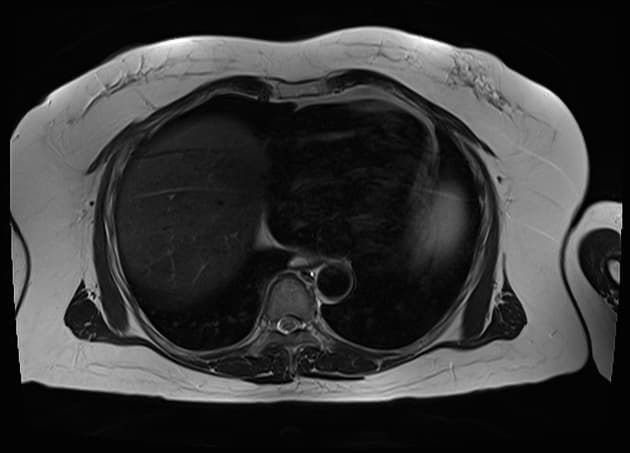

Series (7)

Coronal C+ arterial phase

Có khối giảm tỷ trọng (hypodense) kích thước 15 x 18 x 35 mm nằm tại tuyến thượng thận trái, hình ảnh không thay đổi so với phim chụp bên ngoài cách đây 2 năm – độ cản quang dưới 10 HU. Trong thân tụy, thấy tổn thương khối giảm tỷ trọng kích thước 24 x 25 x 21 mm, phù hợp với (consistent with) tiền sử ung thư tụy đã biết. Các vôi hóa (calcification) dạng lớn thấy kề cận trong nhu mô tụy.

Thấy tổn thương mô mềm bất thường quanh trục thân tạng (celiac axis) và kề cận động mạch mạc treo tràng trên (SMA) – gợi ý (suggestive of) tổn thương di căn (metastasis). Tổn thương này dường như tách biệt với khối u nguyên phát tại tụy. Không thấy hình ảnh di căn (metastasis) khác trong ổ bụng. Không thấy bệnh lý hạch (lymphadenopathy) tại ổ bụng, tiểu khung hay vùng hậu phúc mạc (retroperitoneum).

Khối giảm tỷ trọng tại thân tụy phù hợp với (consistent with) tiền sử ung thư nguyên phát tại tụy (primary pancreatic malignancy), với tổn thương di căn (metastatic disease) nghi ngờ quanh trục thân tạng và kề cận đoạn gần động mạch mạc treo tràng trên (SMA). Khối ổn định tại tuyến thượng thận trái.

Hình ảnh phóng đại tại thân tụy và đánh giá tổn thương mạch máu: khối u bao quanh (encasement) động mạch lách, thân tạng, động mạch gan chung và điểm xuất phát của động mạch vị trái. Ngoài ra, khối u tiếp cận và xâm lấn dưới 180 độ vào động mạch mạc treo tràng trên (SMA).

Ca lâm sàng này minh họa một trường hợp ung thư biểu mô ống tụy không cắt bỏ được (unresectable pancreatic ductal adenocarcinoma) do khối u bao quanh hoàn toàn (complete encasement) thân tạng và các đoạn gần của các nhánh mạch (bệnh lý giai đoạn T4).